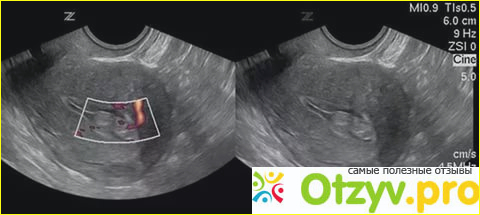

На узи есть полип

На узи есть полип 115 фото